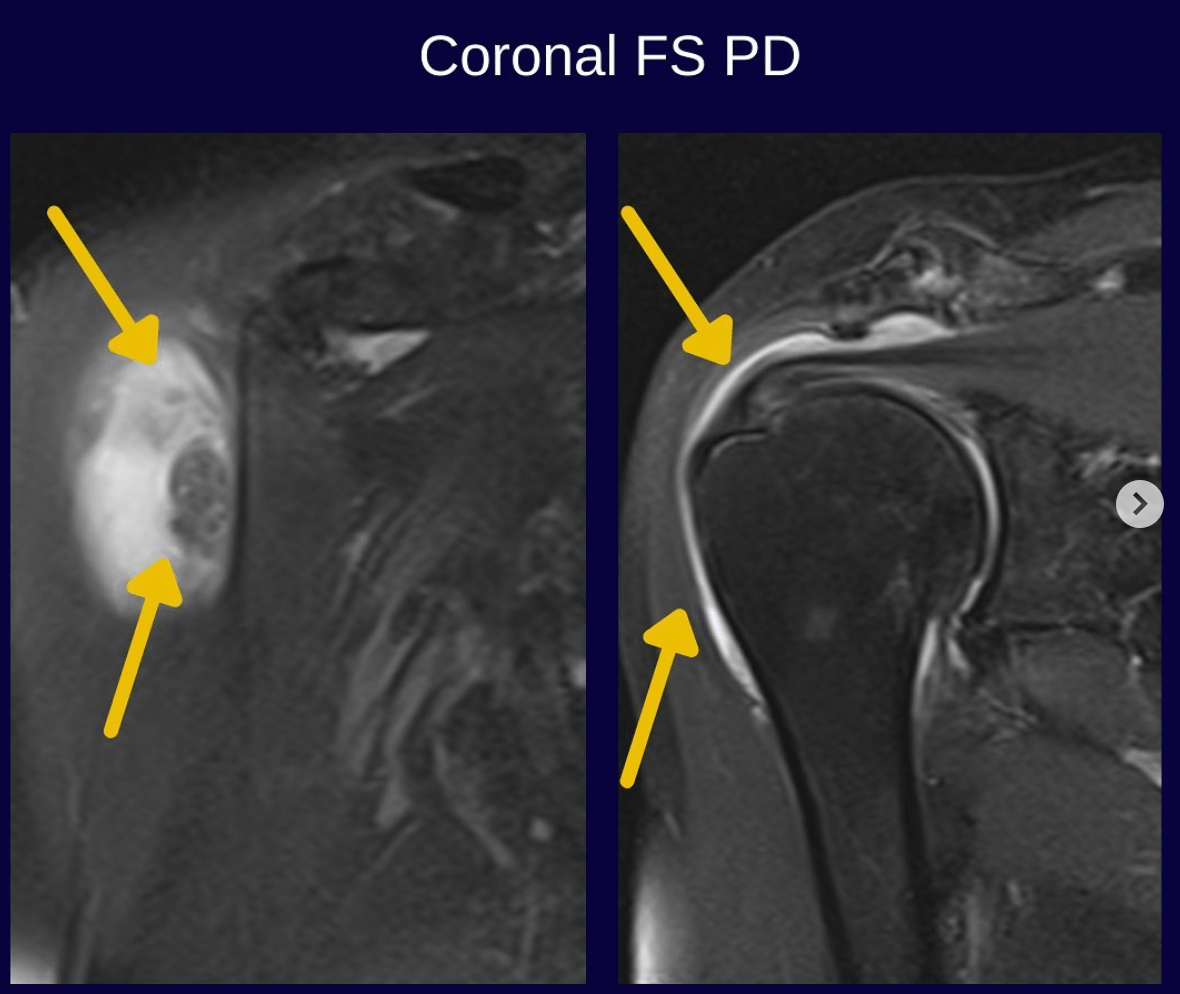

From Rachael Gordon, A neuron who reads TMJ’s. Great points! Phil, I have seen the pterygoid atrophy. Mostly in patients with head and neck CA who have had XRT. This is better seen on axial images, which can be worth adding, especially if the patient has trismus. I have seen the disc tear like this […]